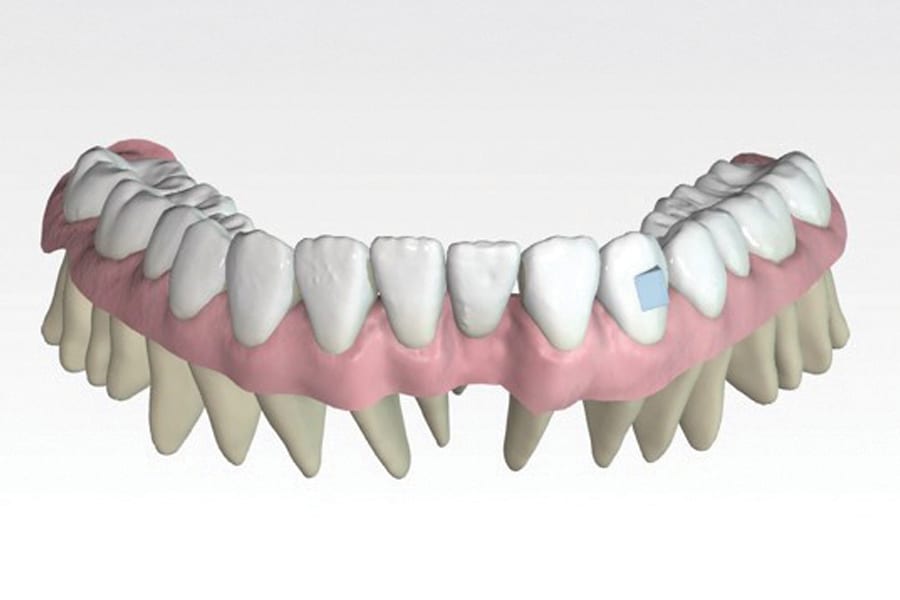

A second alternative is a laboratory-processed nickel-titanium splint (Figure 3) (Memotain®, AOA Lab, aoaaccess.com). The splint is manufactured via laser etching from a sheet of material conforming to a digital impression that is sent to a laboratory. Because the wire is not bent from stock, it is passive in nature and has no uncoiling tendency. It conforms accurately to tooth surfaces and is comfortable due to its streamlined design and intimate conformity. These characteristics also make it suitable as a splint when teeth are imperfectly aligned, as in a periodontally involved crowded dentition (Figure 4). Drawbacks of this design are the time and expense of laboratory fabrication.